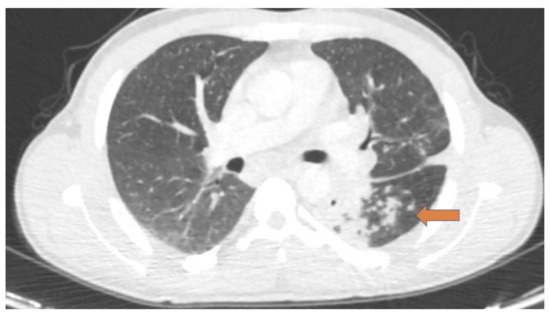

2.1. Pulmonary Schistosomiasis

- Cimini, A.; Ricci, M.; Chiaravalloti, A.; Crocco, A.; Russo, F.; Schillaci, O. A rare case of pulmonary schistosomiasis: 18F-fluorodeoxyglucose positron emission tomography/computed tomography findings. Indian J. Nucl. Med. 2020, 35, 336–338. [Google Scholar] [CrossRef] [PubMed]

- Foti, G.; Gobbi, F.; Angheben, A.; Faccioli, N.; Cicciò, C.; Carbognin, G.; Buonfrate, D. Radiographic and HRCT imaging findings of chronic pulmonary schistosomiasis: Review of 10 consecutive cases. BJR Case Rep. 2019, 5, 20180088. [Google Scholar] [CrossRef]

- Gobbi, F.; Buonfrate, D.; Angheben, A.; Beltrame, A.; Bassetti, M.; Bertolaccini, L.; Bogina, G.; Caia, S.; Duranti, S.; Gobbo, M.; et al. Pulmonary nodules in African migrants caused by chronic schistosomiasis. Lancet Infect. Dis. 2017, 17, 159–165. [Google Scholar] [CrossRef]